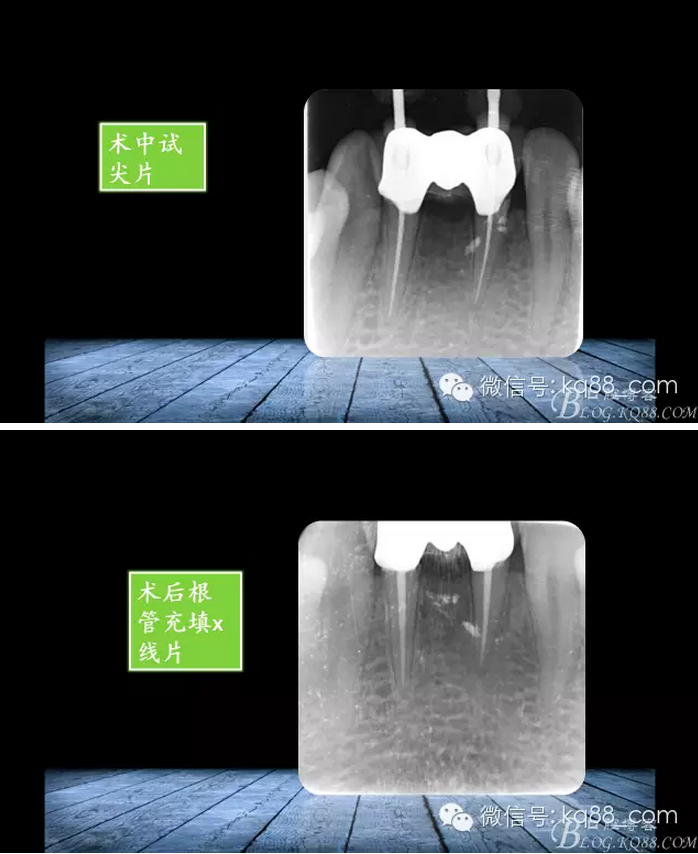

QQ圖片20150817140731.png

QQ圖片20150817140748.png